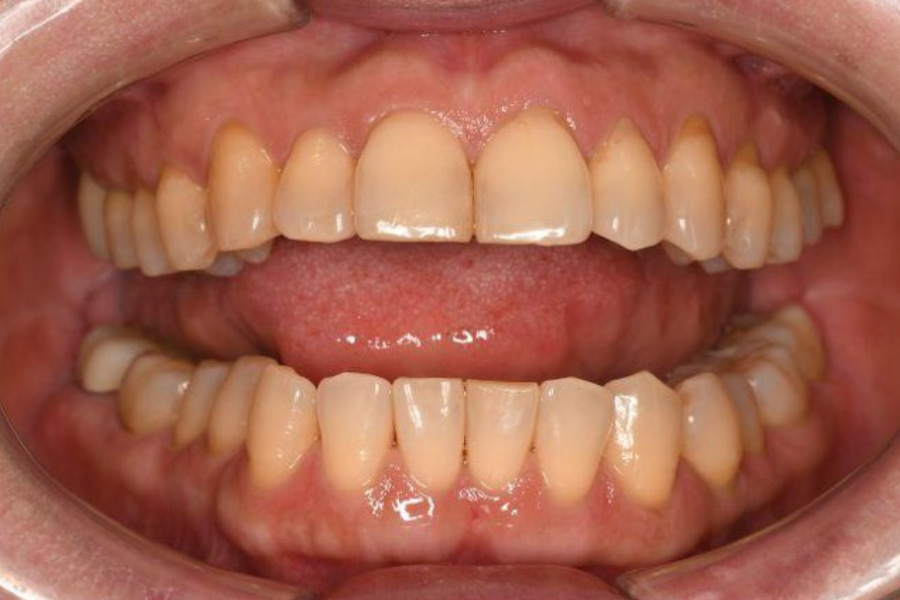

治療前

治療後

| 主訴 | 左奥歯が仕事が忙しくなると上下とも痛くなる。 毎月メインテナンスしていた歯科医院が閉院した。 歯周病含め今の状態が気になる。 全体のメインテナンスもしたい。矯正治療はやりたくない。 |

| 治療内容 | 全顎治療:歯周病治療、根管治療、 歯肉弁剥離掻爬術(フラップ手術)、 セラミック治療、ダイレクトボンディング |